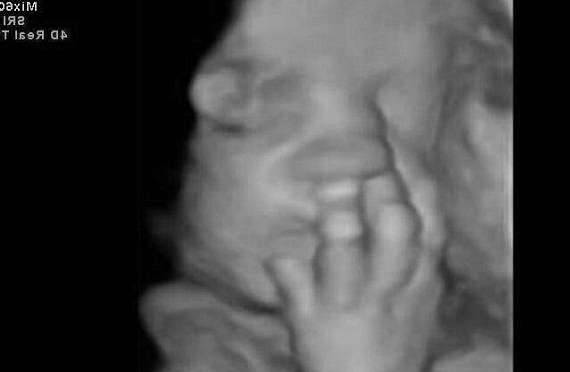

▼这个宝宝则在打自己的脸,他的动作从超音波照片中看得一清二楚。